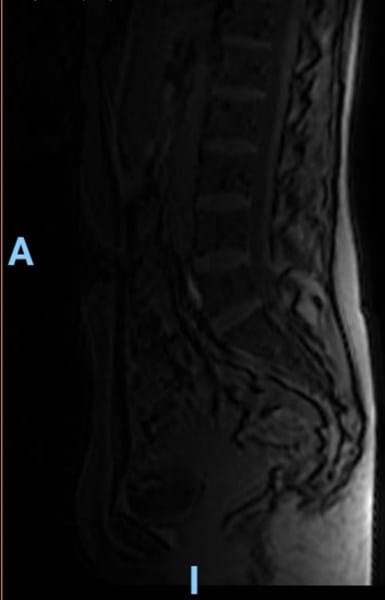

Buenas tardes, me han hecho una resonancia porque me duele mucho la espalda. Hace tiempo (meses) me caí y desde entonces tengo dolor pero no ven nada en la resonancia. Adjunto dos imágenes para tener una segunda opinión.